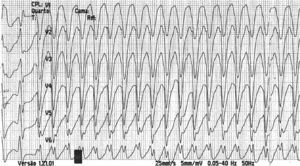

The patient was readmitted to our hospital one year after the previous hospitalization due to multiple ICD shocks, preceded by syncope, with transient recovery of consciousness following each shock, beginning 24 hours previously and increasing in frequency in the hour before admission. He had discontinued his medication in the previous five days due to financial difficulties, since when he had complained of anorexia, asthenia, constipation and dizziness. On admission he was conscious, oriented, and sweating but with no signs of peripheral hypoperfusion. The electrocardiogram (ECG) documented monomorphic VT with complete left bundle branch block and a rate of 300 bpm (Figure 1). A 300-mg bolus of amiodarone was administered followed by intravenous (IV) perfusion at 4 μg/kg/min, but recurrence of VT (with constant morphology on telemetry) was observed; two boluses of IV lidocaine (total 150 mg) were administered but also had no effect. The patient received multiple ICD shocks immediately after arrival at the hospital, resulting in the rapid exhaustion of the generator before the cardiologist was able to inhibit the therapies with the aid of a magnet. During periods of sinus rhythm, the ECG documented QRS with complete right bundle branch block, PR interval at the upper normal level, and corrected QT interval of 405 ms, with no signs of acute ischemia (Figure 2). Transthoracic echocardiography showed a severely dilated left ventricle, with diffuse hypokinesia and severely impaired global systolic function. Interrogation of the CRT-ICD revealed various episodes of VT in the previous 24 hours, with a total of 48 appropriate shocks (Figure 3), and the generator at the end of battery life. Given the patient's worsening heart failure and persistence of the arrhythmic storm, he was intubated and given propofol and midazolam for sedation and analgesia. Laboratory tests at admission showed acute kidney injury (Acute Kidney Injury Network stage 1) with creatinine 1.5 mg/dl and urea 101 mg/dl; mild hypokalemia (potassium 3.0 mmol/l, normal range 3.5-5.1); severe hypercalcemia (calcium 18.5 mg/dl, normal range 8.6-10; Ca2+ 2.46 mmol/l, normal range 1.13-1.32); and slight elevation of troponin I (peak 1.5 mg/dl, cutoff <0.07). The hypokalemia was immediately corrected.